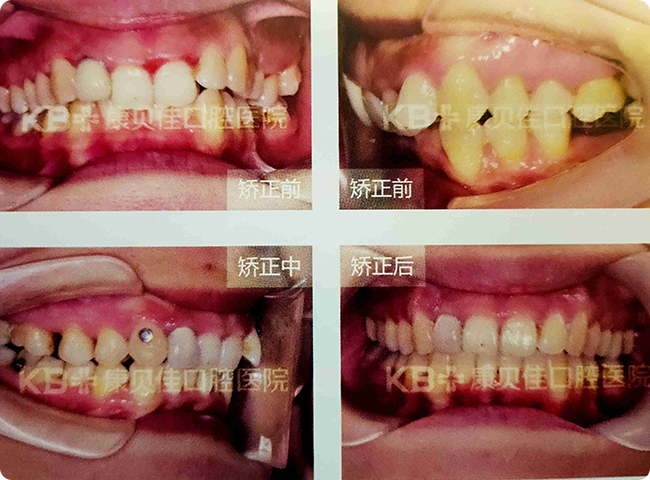

王女士

24岁

牙齿不齐,缺乏自信。

治疗方案:

通过隐形矫正,排齐牙列,对矫正效果很满意。